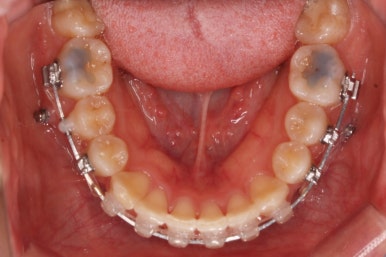

아랫니에도 이제 장치를 붙였습니다.

아랫니도 어느 정도 많이 가지런해졌습니다.

이제 아래쪽도 당겨 넣습니다.

원하는 만큼, 허락하는 만큼 계속 당겨 넣습니다. 연산동교정치과에서는 비발치 돌출입 교정을 위해 총 4개의 미니스크류를 식립했습니다.